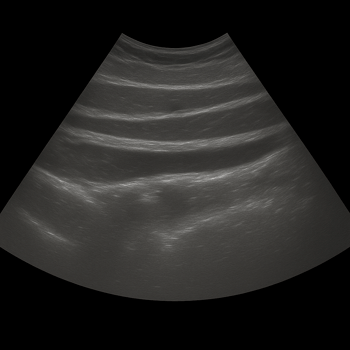

Ultrasound – A Gentle and Accurate Method

Unlike CT scans, ultrasound uses no radiation. The main advantage is that the examination is dynamic. This means the doctor can observe the hernia in real-time while you cough or tense your stomach. This allows even the smallest hernias, which might otherwise stay hidden, to be identified.

During an examination, one can determine:

• Hernia orifice size: How large is the opening in the abdominal wall?

• Content: Is it fat or bowel bulging out?

• Reducibility: Can the hernia be pushed back easily?